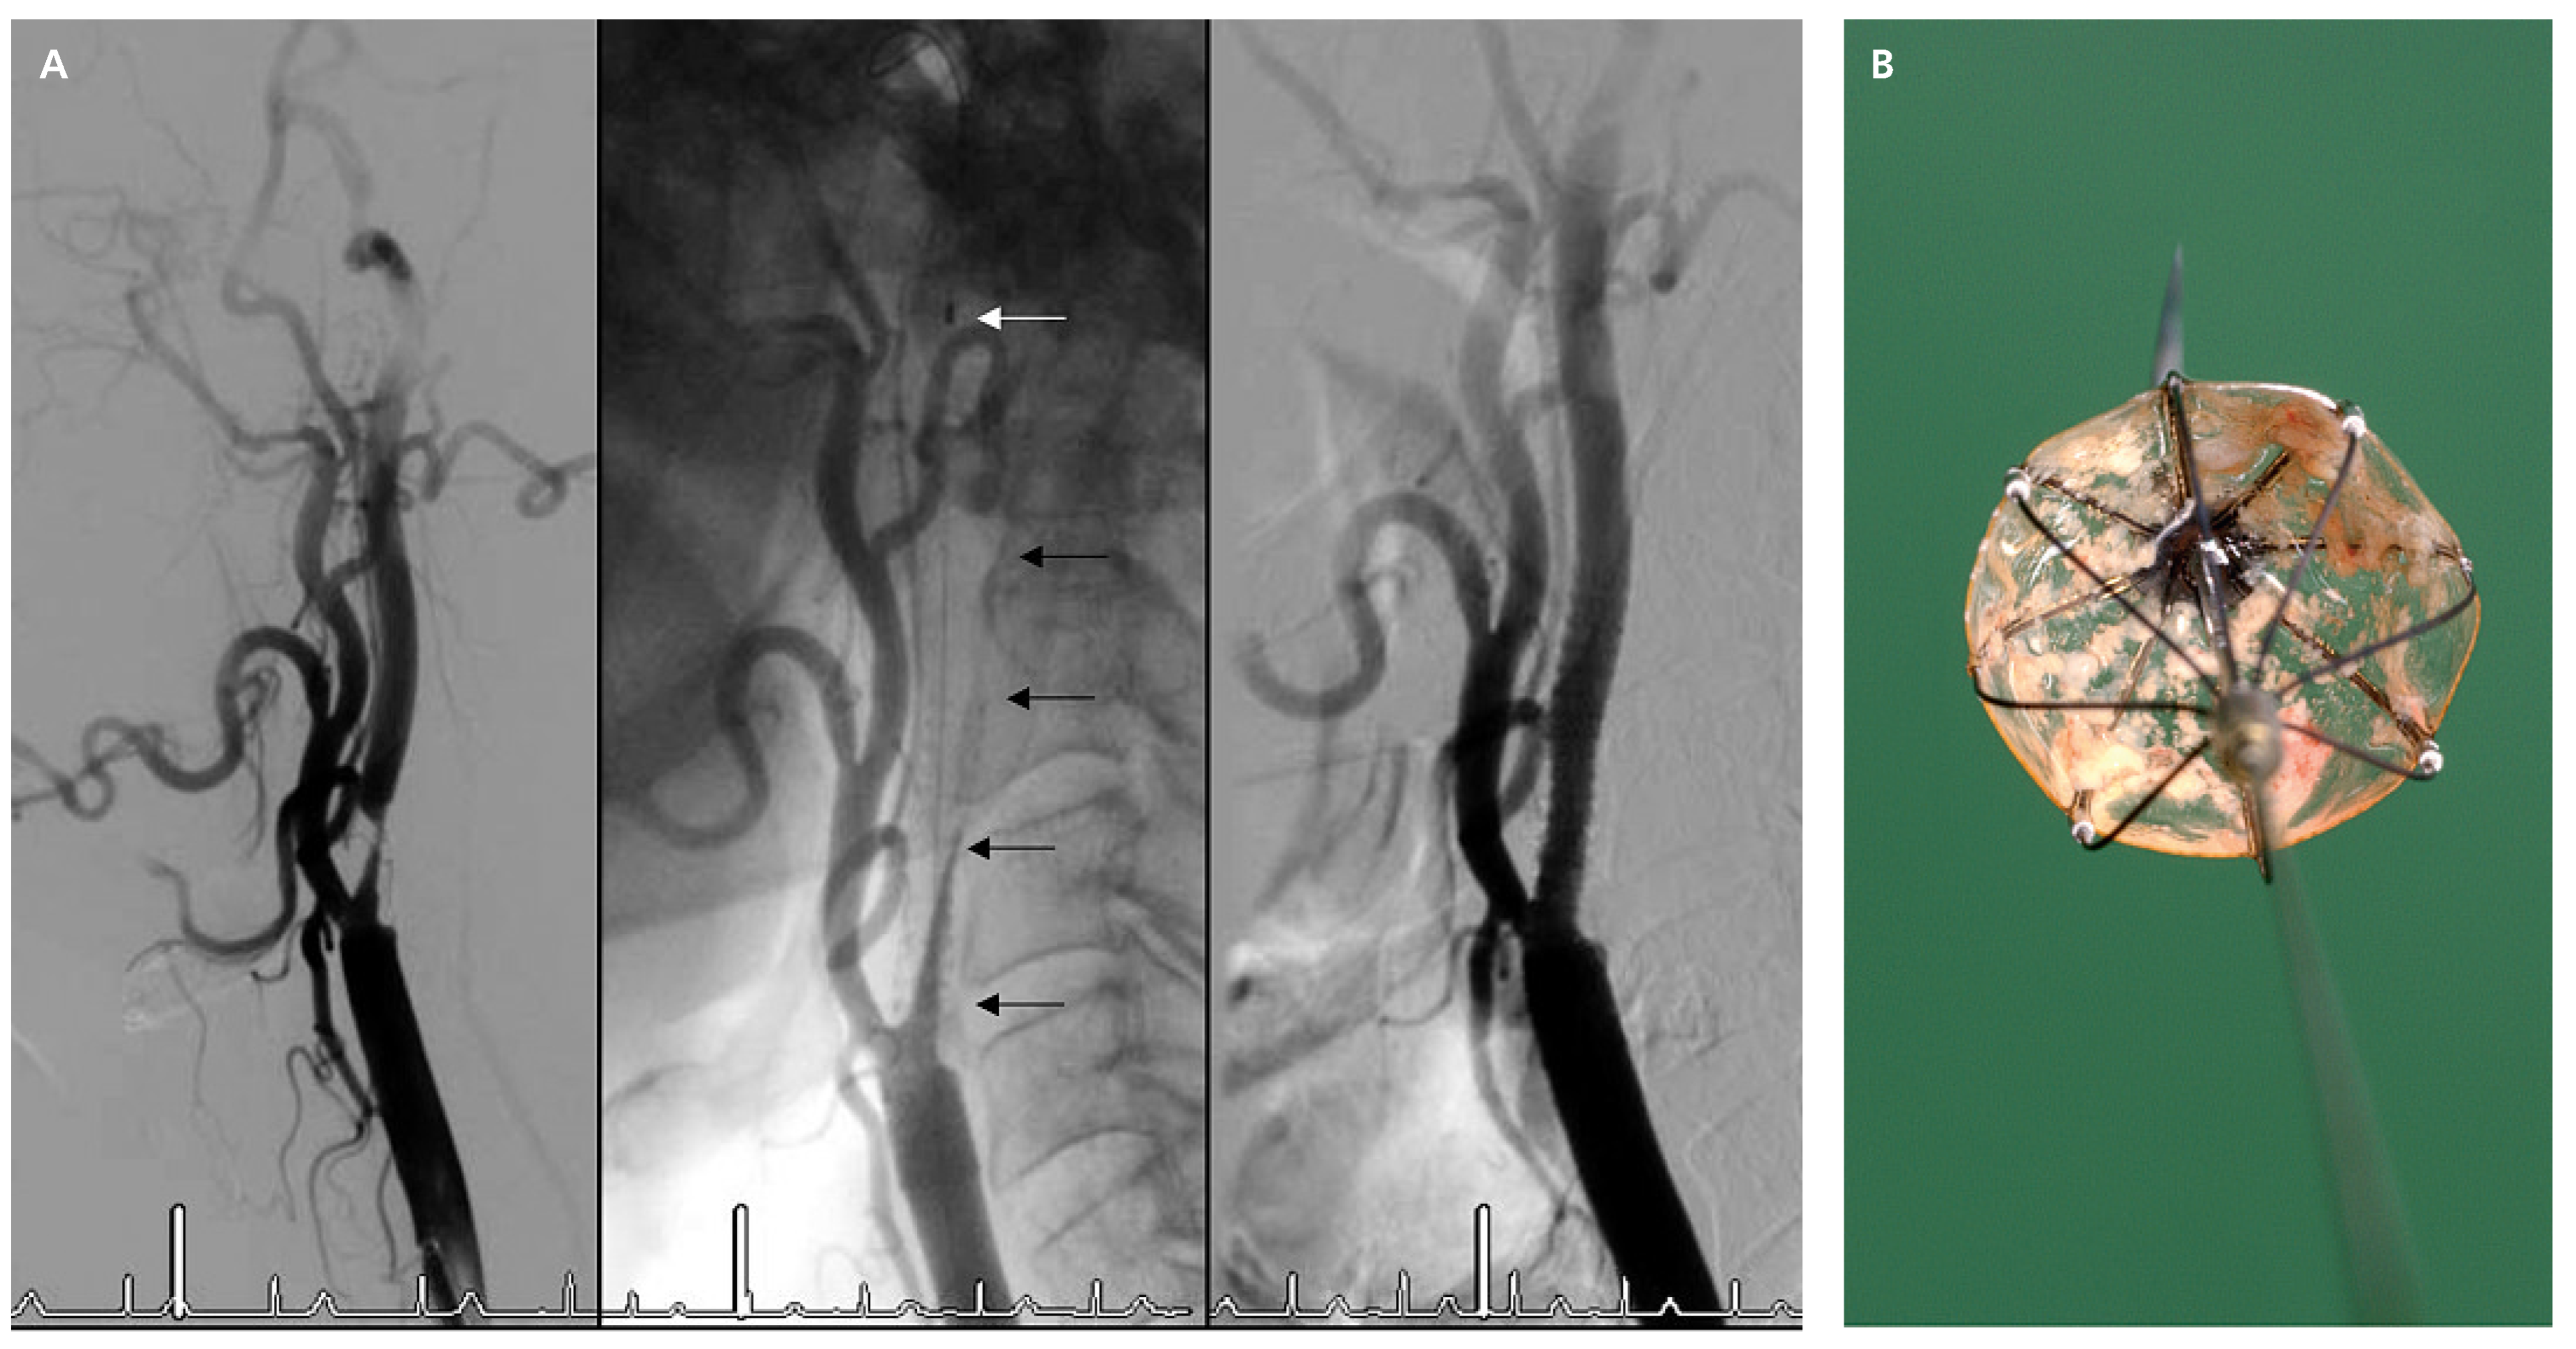

Carotid artery stenting

- Roffi, M.; Baumgartner, R.W.; Eberli, F.R. Images in cardiology. No reflow during carotid stenting. Heart (British Cardiac Society). 2006, 92, 538. [Google Scholar]

- Roffi, M.; Greutmann, M.; Schwarz, U.; Luscher, T.F.; Eberli, F.R.; AmannVesti, B. Flow impairment during protected carotid artery stenting: impact of filter device design. J Endovasc Ther. 2008, 15, 103–109. [Google Scholar] [PubMed]